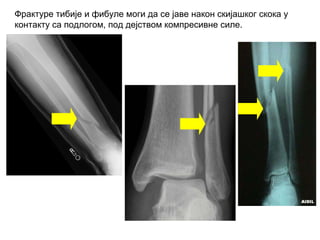

Фрактуре тибије и фибуле моги да се јаве након скијашког скока у

контакту са подлогом, под дејством компресивне силе.